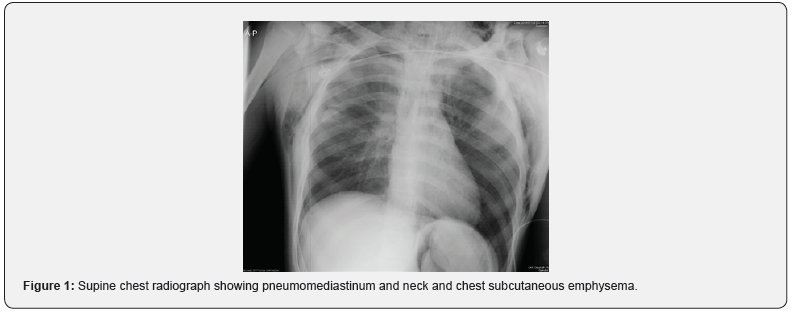

A 17-year-old man arrived in the emergency room after a motor vehicle accident .He was agitated and in respiratory distress with labored breathing and urgently intubated orotracheally. The vital signs included a blood pressure of 110/80 mmHg, a heart rate of 115 beats/ min, and an axillary temperature of 36.4°C. Patient had crepitus on his neck and chest area. . Pneumomediastinum and subcutaneous emphysema were seen on a supine chest radiograph (Figure1). Computed tomographic scan (CT) of the neck and chest revealed pneumomediastinum, pulmonary contusion and subcutaneous emphysema in the neck and chest (Figure2). Because of concern for suspected tracheobronchial injury ,flexible fiberoptic bronchoscopy in the emergency room was performed but no finding in favor of tracheal injury was reported and tracheal transection was miss. During one-week admission of the patient in the ICU ,he had occasionally high peak ventilator pressures but saturated well. On the seventh day due to saturation drop and high peak ventilator pressures ,the flexible bronchoscopy examination was carried out in the operating room. This showed complete tracheal transection in midportion (Figure 3). Neck exploration demonstrated complete tracheal transection. The area was debrided, and primary end-to-end anastomosis was performed. . The patient was extubated at the end of surgery . After one week the patient was discharged.